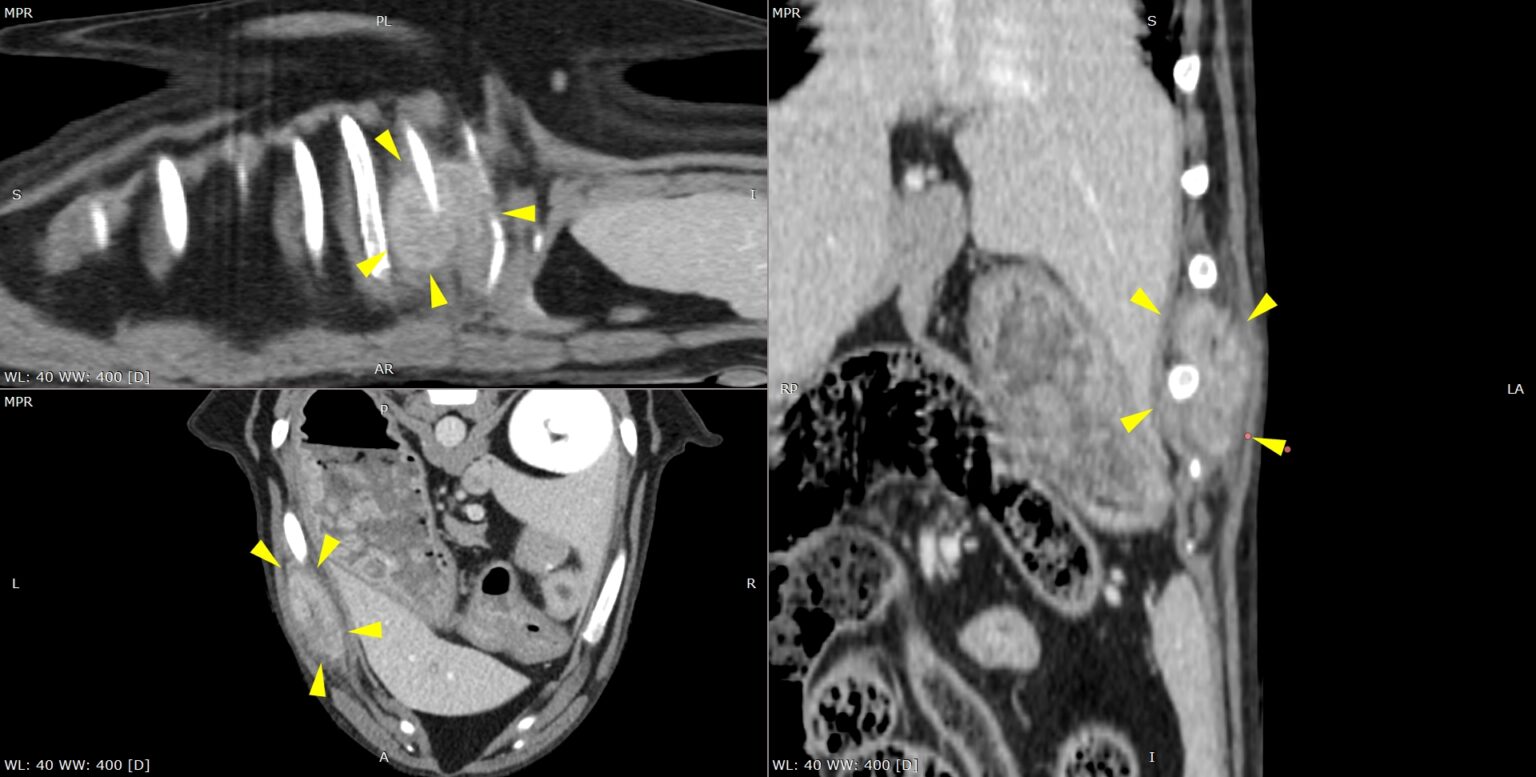

Scanner thoracique en reconstruction multiplanaire (MPR) illustrant un sarcome costal chez un chien.

Les reconstructions dans les trois plans mettent en évidence une masse tumorale infiltrante développée à partir des côtes gauches, avec atteinte des tissus mous adjacents et déformation locale de la paroi thoracique, comme indiqué par les flèches. Ce type d’imagerie permet une caractérisation précise de l’extension osseuse et extra-osseuse de la tumeur, indispensable à la planification d’une chirurgie oncologique large et raisonnée.